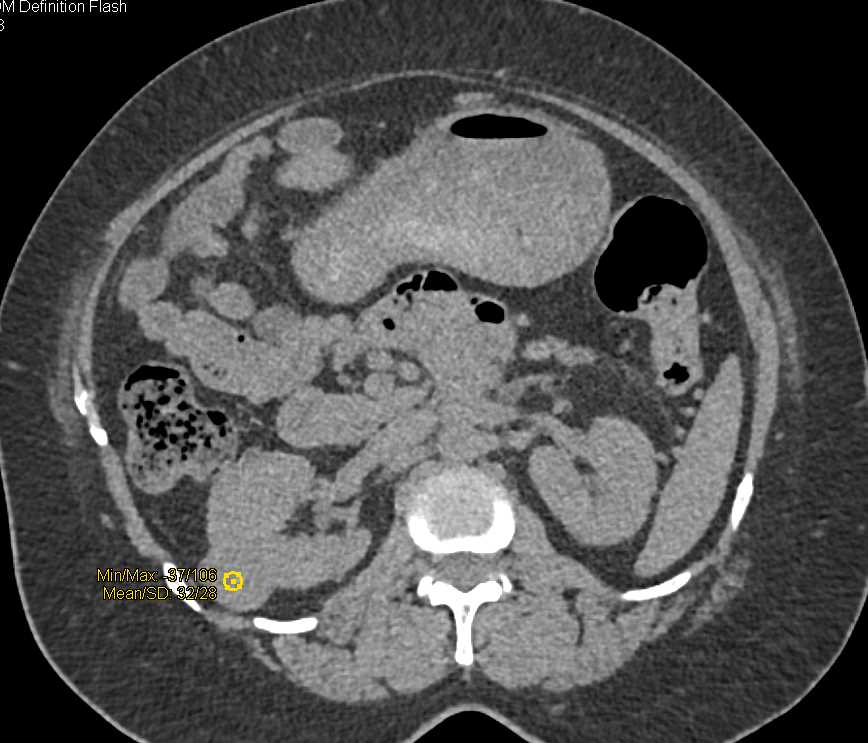

Cystic Renal Cell Carcinoma